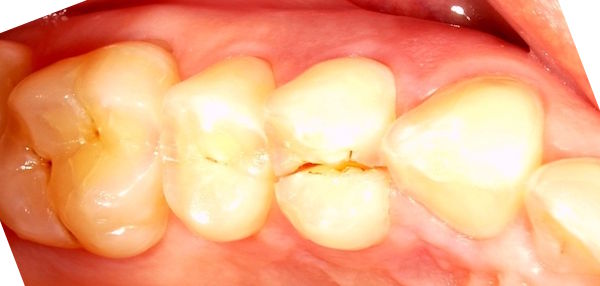

Die Schlifffacette auf dem Weisheitszähnen zeigt einen Bruxismus an.